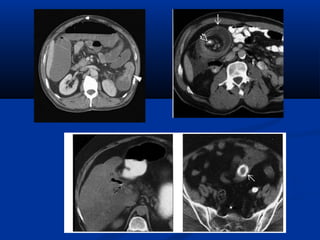

NOÄI SOI AÛOPHEÁ QUAÛN